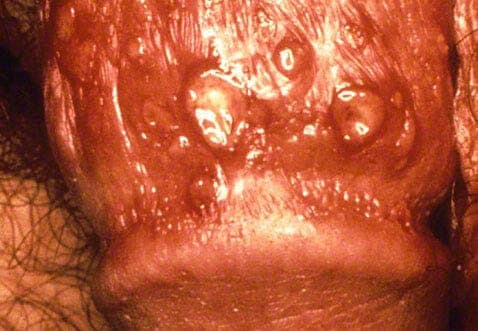

Genital herpes symptoms

Genital herpes symptoms can develop fast with discomforting and sometimes painful red blisters (lesions) and skin ulcers forming in the genital area, the thighs, anus and rectum. The blisters can also be painful when they burst, leaving open sores that are easily irritated. You may also experience:

• Tingling sensation

• Burning sensation

• Fever

• Pain when you urinate

• Unusual vaginal discharge

Both initial and later outbreaks will display symptoms such as red blisters, ulceration and a tingling or burning sensation around the genitals, however the first outbreak will usually be the most severe and have some additional factors. Along with the usual symptoms, these will be more painful the first time, but luckily this decreases after.

As well as blisters, tingling, pain when urinating and vaginal discharge in women, the first outbreak may be accompanied by flu and cold symptoms like muscle aches, fever and nausea. The initial outbreak also tends to be the longest in length, with the recurrent virus becoming far more manageable over time.